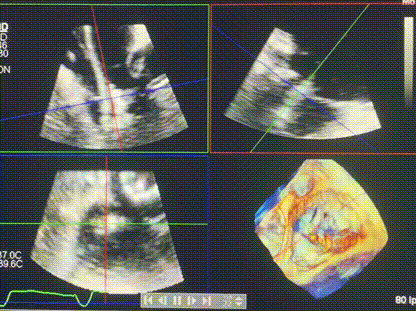

術后超聲顯示僅殘余微量瓣周漏

LuX-Valve Plus經血管三尖瓣置換系統此次“出海”圓滿完成,術后Rodrigo Estévez-Loureiro教授對LuX-Valve Plus經血管三尖瓣置換系統的器械性能和治療效果大為稱贊,認為LuX-Valve Plus的手術體驗非常好。術后即刻超聲顯示三尖瓣反流幾乎完全消失,血流動力學改善顯著,患者恢復快。在面對復雜解剖結構、超聲影像質量不佳、有起搏導線干擾時,Lux-Valve Plus也體現了極強的適應性。Thomas Modine教授和Anson Cheung教授也肯定了LuX-Valve Plus術中操作的便捷性,認為LuX-Valve Plus容錯率高,對術中影像的依賴較小,后期希望可以更多的應用LuX-Valve Plus三尖瓣置換系統于臨床實踐,讓更多的三尖瓣重度反流患者盡早獲益,改善預后。